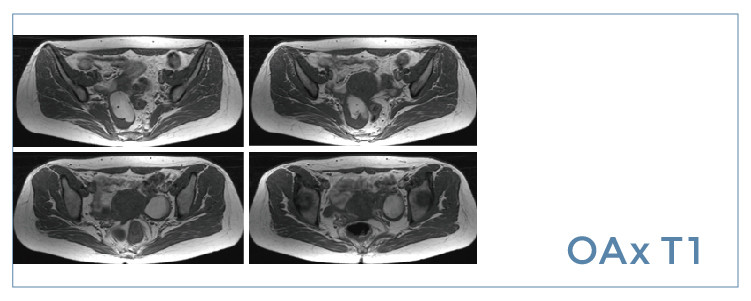

【朗润影像档案】磁共振影像病例分享(编号20190726)